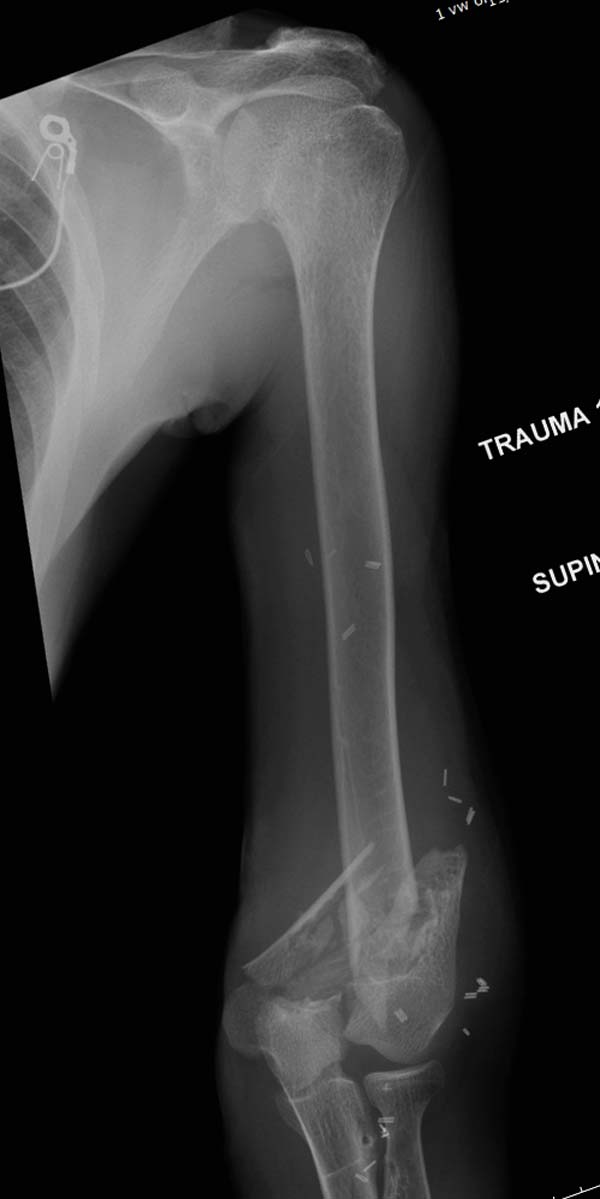

Больному 25 лет, транспортная травма. С детства хроническая почечная

недостаточность, постоянный гемодиализ, находится в листе ожидания на

пересадку почки. Около 4 года назад автоавария с двухсторенним переломом

ацетабулум, которая слева закончилось тотальным протезированием.

Диагноз: переломы бедренных костей, перелом дистального плеча слева,

также неосложненный перелом на уровне грудных позвонков.

Рентген снимки. Хотели услышать примерный алгоритм лечения, c чего

начать и как?

Имя     : 1 Periprosthetic IM nail pelvis.jpg